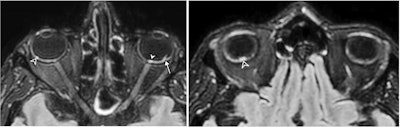

The investigators found that nine (7%) of the COVID-19 patients had abnormal MRI findings on the globe, or eyeball, with one or more nodules on the posterior pole. All these patients had nodules in the macular region, or the area of the eye responsible for central vision, and eight had nodules in both eyes (89%).

Why the nodules formed in these patients is unclear, although Lecler and colleagues hypothesized it could be due to inflammation caused by the virus or to inadequate draining of veins in the eyes in patients who spend time in the intensive care unit (ICU) in a prone position or intubated. In fact, eight of the nine patients who had abnormal eye findings on MRI were admitted to the ICU, and seven of these were in the prone position in the ICU for long periods, the group noted.